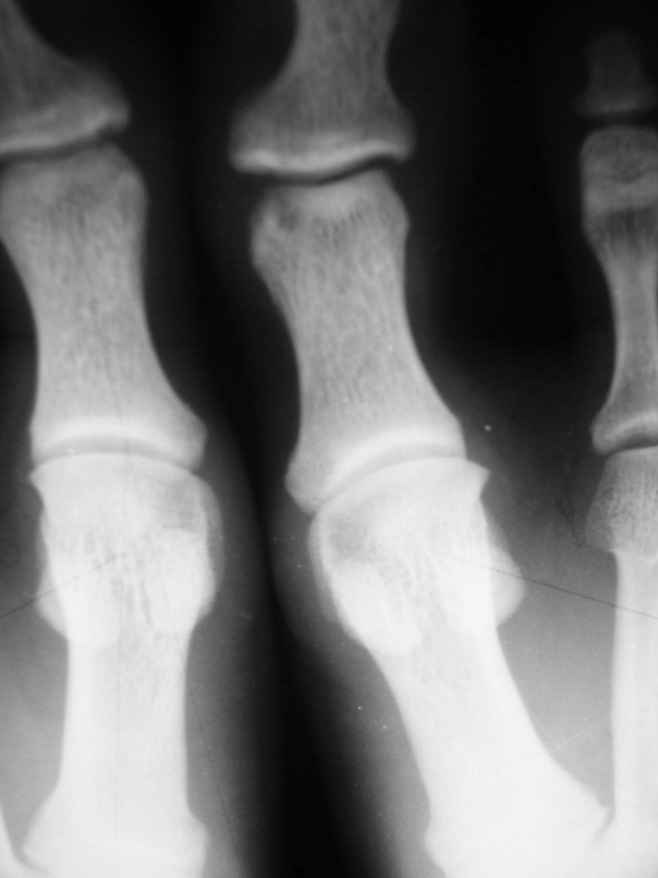

1-Пациент Х.18лет, аневризмальная костная киста малоберцовой кости и основной фаланги I пальца левой стопы (Рис. 1,2).